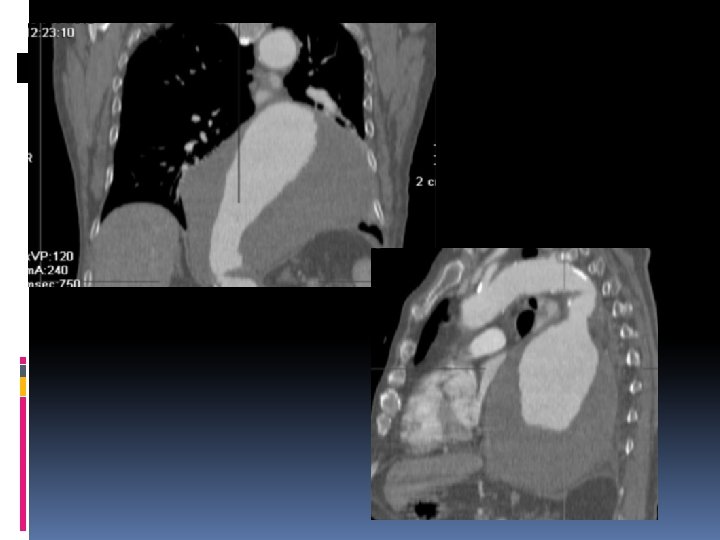

Hematoma Intramural Disección aórtica sin puerta de entrada. Atribuible a rotura de los vasa vasorum. Evolución: reabsorción, disección clásica o ruta arterial.

Hallazgos radiológicos No aporta nada la angiografía. Sangrado fresco en pared de aorta sin C. iv. Desplazamiento de las calcificaciones de la íntima. Trombosis frec. En la luz del hematoma.

Protocolo de CT Estudio basal Tórax o Tórax-Abdomen. 120 -150 cc, 3 -5 cc/s. Cortes de 3 0 5 mm. Estudio en fase arterial: Sure Star Delay Fijo (25 segundos). Estudio tardío. Reconstrucciones MPR y MIP.

Úlcera Arteriosclerótica Penetrante Placa ateroesclerótica que tras una erosión y ulceración inicial rompe la lámina elástica interna y penetra en la capa media. Más frecuente en aorta torácica. Curso clínico impredecible. Progresión hacia DA, pseudoaneurisma…

Hallazgos Radiológicos En CT: úlcera focal que se extiende hacia hematoma subíntimo. Mejor diagnóstico mediante angiografía.